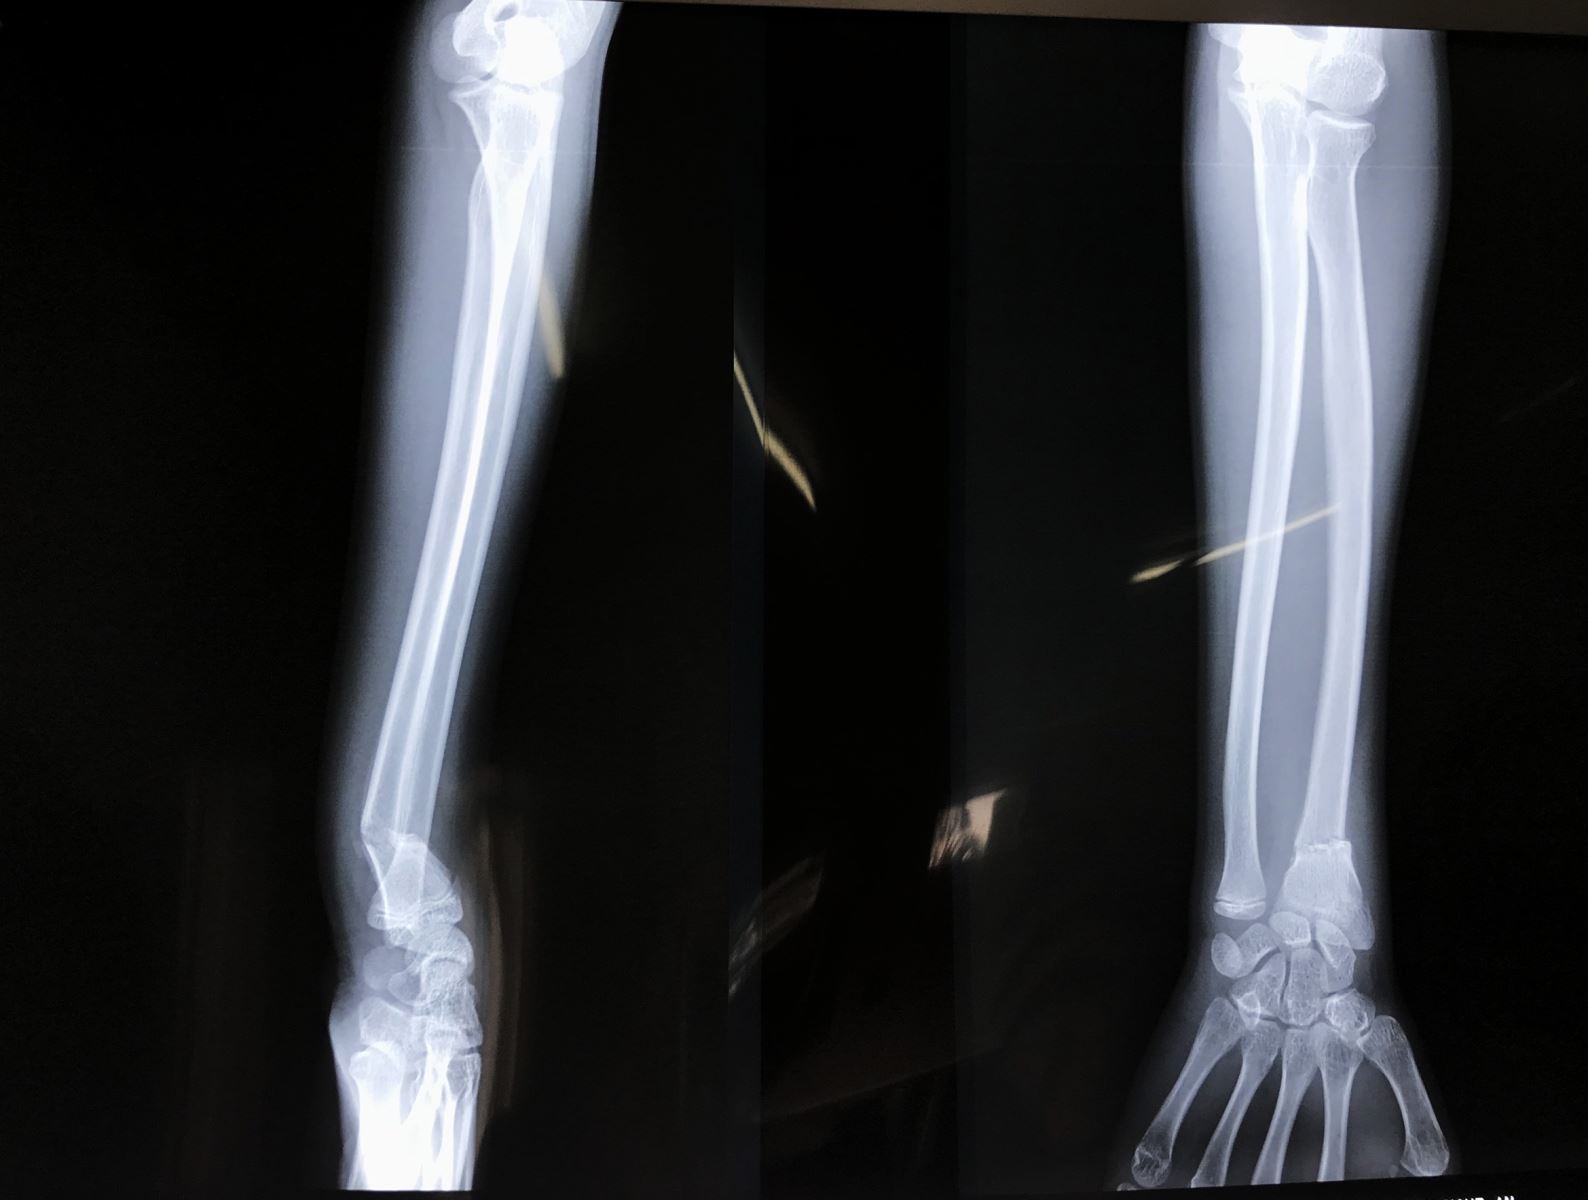

2. Cận lâm sàng

- X Quang cổ tay, cẳng tay thẳng nghiêng

X Quang khuỷu tay thẳng nghiêng nếu có đau về phía khuỷu hoặc có gãy thân xương